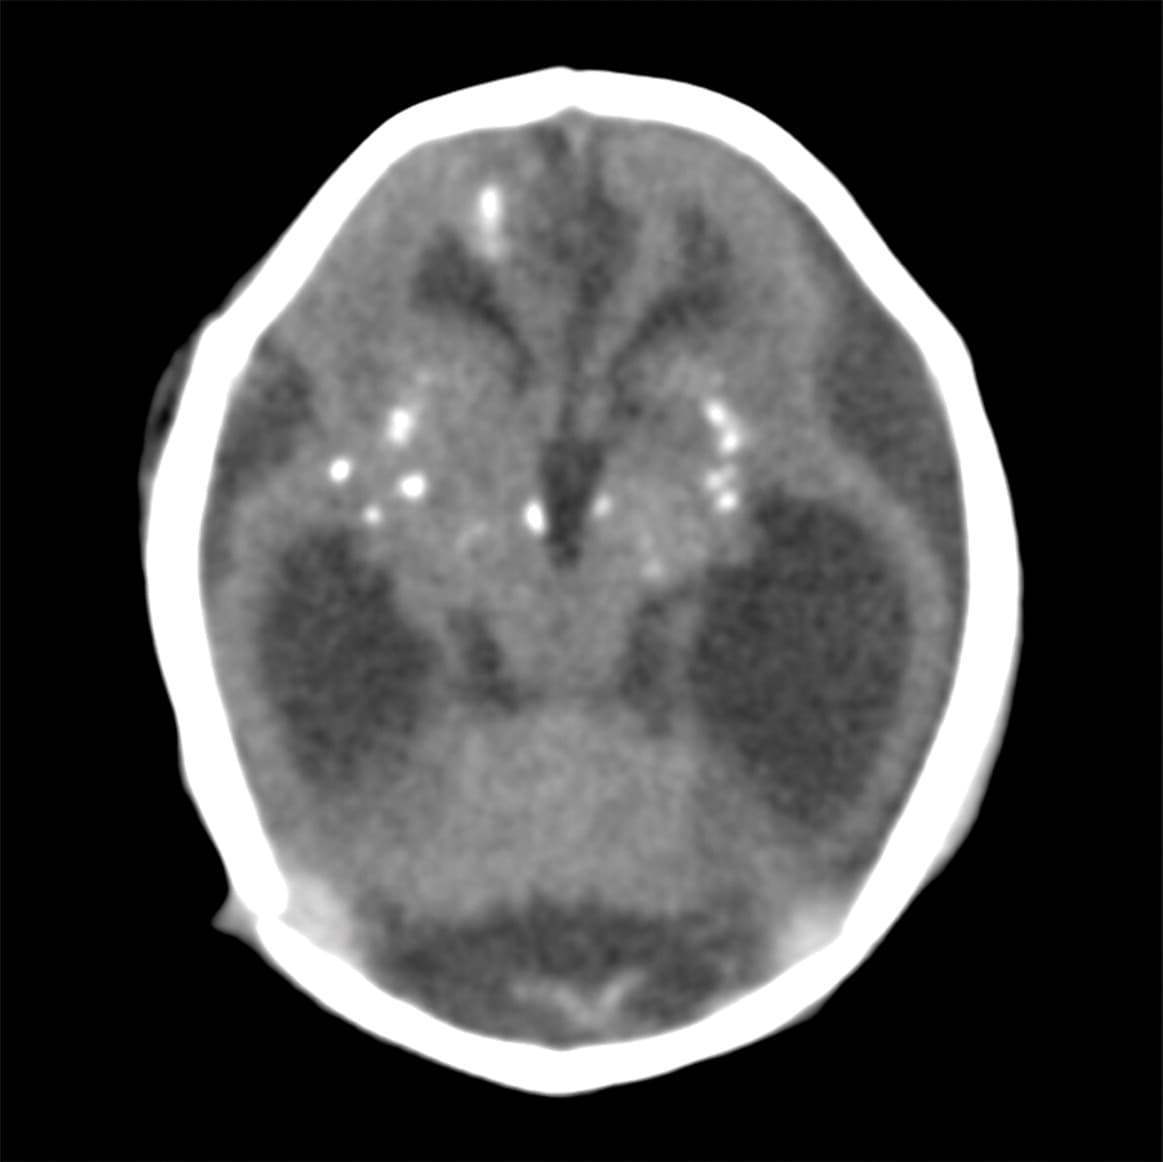

El feto falleció. Las imágenes computarizadas muestran que tenía calcificaciones en la materia blanca, el tálamo y los ganglios basales.

Radiology.

No tenía el cuerpo calloso que conecta ambos hemisferios.